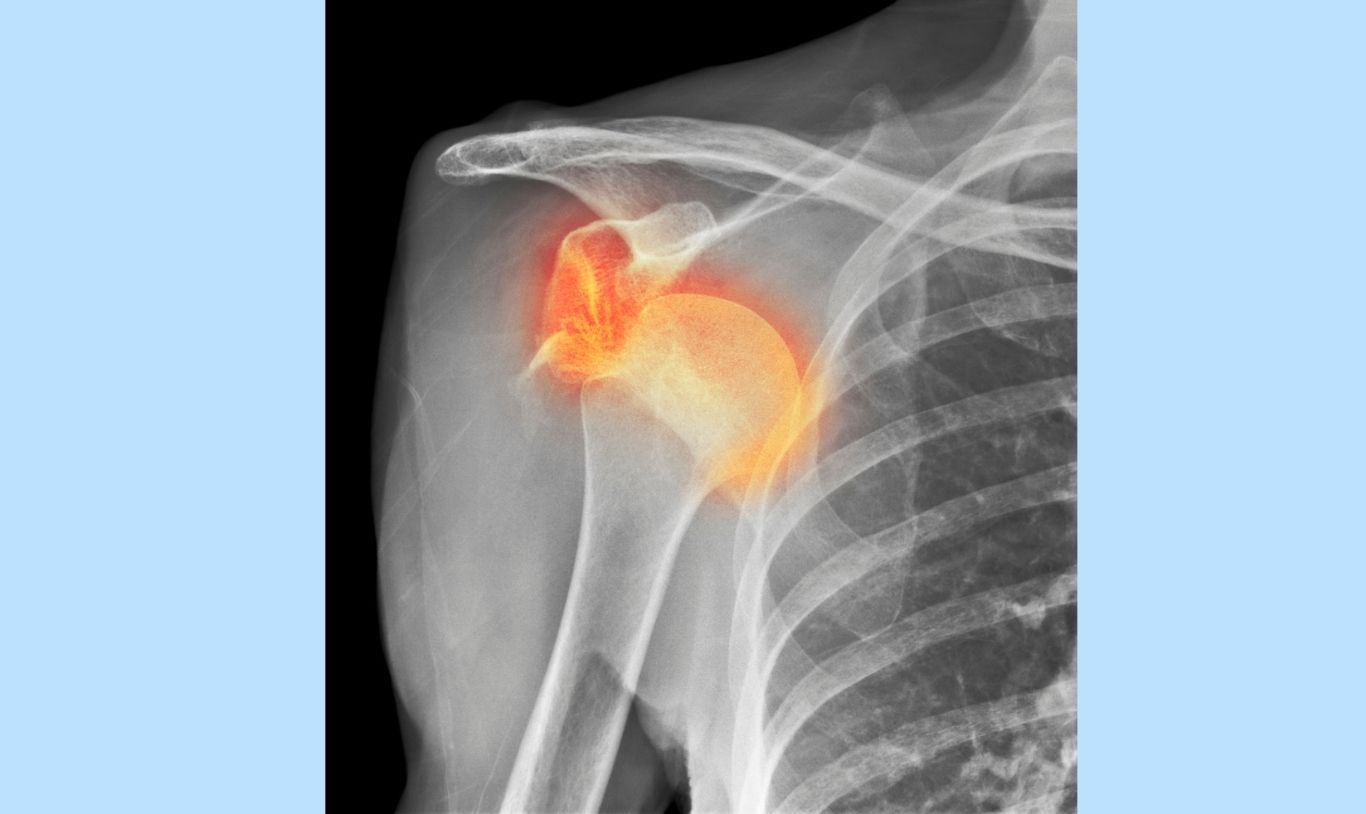

Rugby is an intense contact sport. Shoulder injuries are very common in rugby. They include:

- Dislocated Shoulders: A player can dislocate their shoulder, resulting in damage to the muscles and ligaments. These require immediate medical attention, i.e. being put back in place, as soon as possible to prevent further damage. Recurring shoulder instability is very common after a dislocation. Optimal rehabilitation is essential for stability after dislocation.